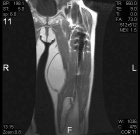

A.M. - 87 year old female with an asymptomatic posterior thigh soft tissue mass present for many years, the patient reports that it has increased in size over the past three months